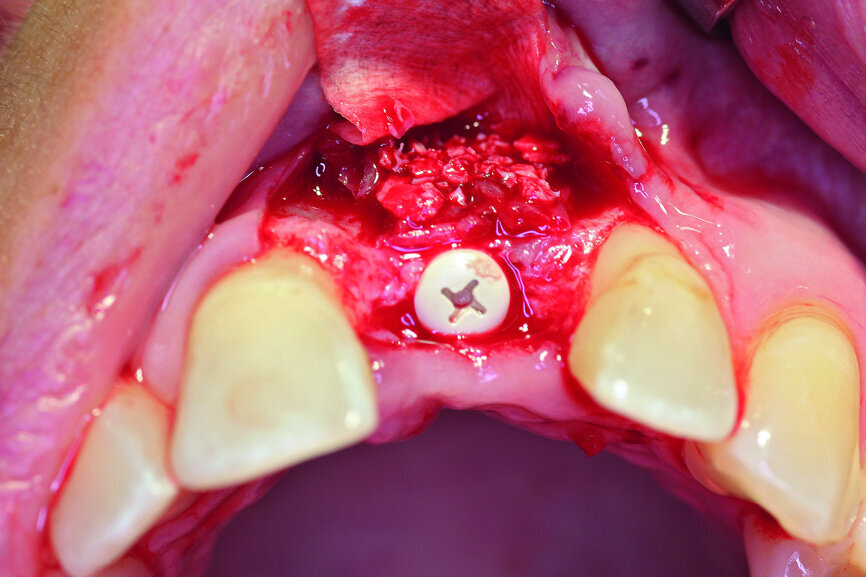

Fig. 6a: Transversal bone augmentation was performed.

Fig. 6b: Transversal bone augmentation was performed.

After extraction of tooth #21, the apical granulation tissue was excochleated through a semilunar incision (Fig. 3). A two-stage procedure was performed to prevent failure of osseointegration of the ceramic implant and to preserve the soft-tissue structures (papillae and attached gingiva). A claspless prosthesis made from Valplast (Valplast International) served as a temporary restoration. The implant site in region #21 was uncovered after five months (Fig. 4). A two-piece ceramic implant (diameter: 4.2 mm; length: 12.0 mm) was then inserted (Figs. 5a & b). The guidelines for implant placement in the aesthetic zone and the drilling procedure specified by the manufacturer were observed.13, 14 Both vertical and transverse insertion depth are decisive for prosthetic success. The implant can be placed between 1.6 mm and 0.6 mm supracrestally because of a special thermal etching procedure in the collar region; the insertion depth is determined by the gingival height and the existing bone of the adjacent teeth. The implant positioning should be approximately 2–3 mm subgingivally because the abutments are added 1 mm above implant shoulder level. Transversal bone augmentation was performed with a mixture of autogenous bone chips (retrieved from the retromolar mandible), xenograft (Geistlich Bio-Oss, Geistlich Biomaterials) and guided bone regeneration (Jason membrane, botiss biomaterials; Figs. 6a & b). The exposure was performed after four months using a PEEK gingiva former (Fig. 7).